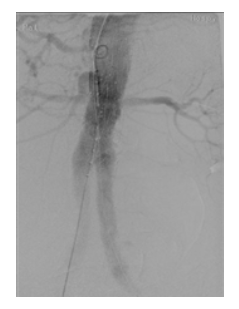

The final completion angiogram demonstrated perfusion of bilateral renal arteries, resolution of the Ia endoleak and without further endoleaks, as well as perfusion of both hypogastric arteries (Figure 5). At two months of follow-up, the patient remains asymptomatic and the angio-CT scan showed resolution of type Ia endoleak (figure 6) and the presence of a late type II endoleak.

Fig 5: Final completion angiogram. Deployed modified Zenith® CE Fenestrated Stent Graft with patent renal and visceral arteries and absence of endoleaks.